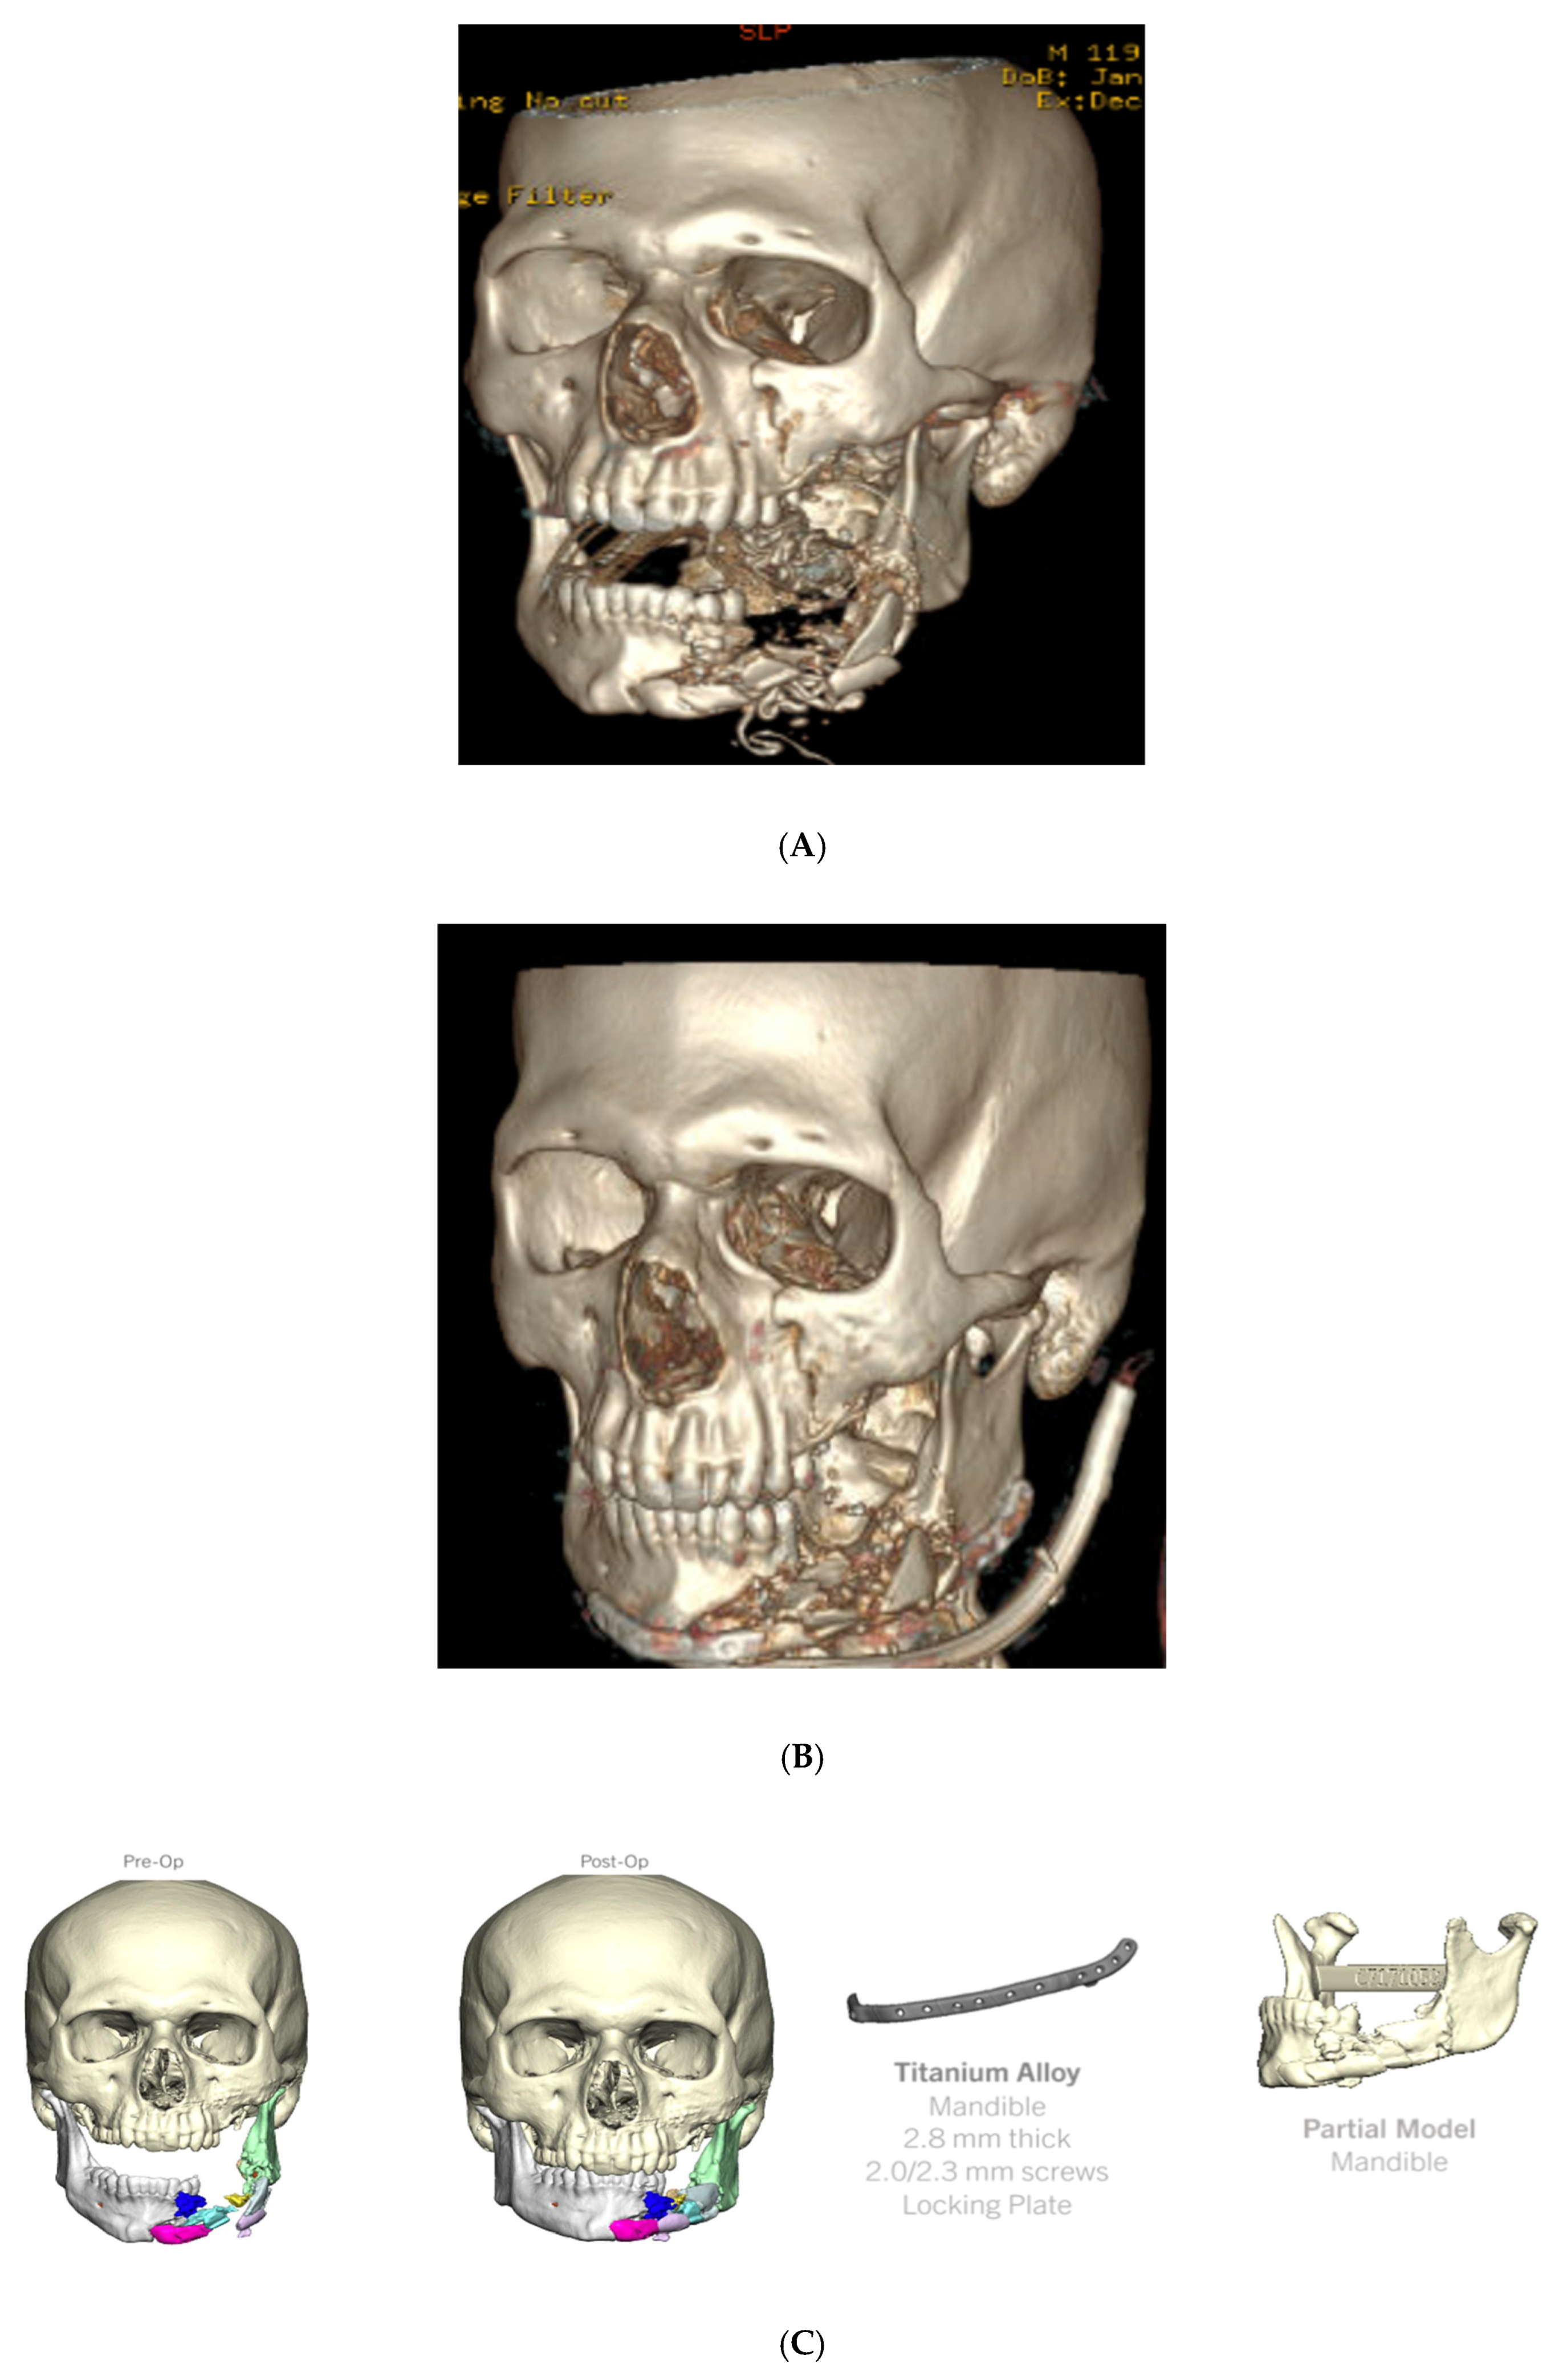

4.3. Case 3 (Patient 3D Model, Occlusal Splint, 3D Printed Plate)

- Left orbital floor and lateral orbital rim fractures;

- Comminuted maxillary fractures with involvement of the hard palate and retained bullet fragments in the maxillary sinus;

- An extensively comminuted open fracture of the left mandibular body extending to the parasymphysis;

- Extensive soft tissue and dental injuries with retained ballistic fragments.

- When ballistic trauma results in excessive comminution and pulverization of bone, VSP can be used to assist with fracture reduction and, if needed, for the production of custom implants that span the areas of bone loss.